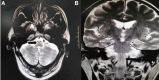

Wernekink commissure syndrome secondary to caudal paramedian midbrain infarction (CPMI) is a rare midbrain syndrome involving the decussation of the superior cerebellar peduncle in the caudal paramedian midbrain tegmentum. The central characteristics are constant bilateral cerebellar dysfunction, variable eye movement disorders, and rare delayed palatal myoclonus. Following is a description of the case of a 60-year-old man who presented with dizziness, slurred speech, and difficulty walking. Neurological examination revealed bilateral cerebellar dysfunction and bilateral internuclear ophthalmoplegia (bilateral INO). Serial magnetic resonance imaging (MRI) revealed a lesion in the caudal paramedian midbrain with a "heart-shaped" sign on fluid-attenuation inversion recovery images and a "V-shaped" appearance on diffusion-weighted imaging (DWI). An acute CPMI with a "heart or V" appearance sign was diagnosed. Upon follow-up evaluation 3 months later, a palatal tremor accompanied by involuntary head tremor was discovered. Hypertrophy and increased signal of the bilateral inferior olivary nucleus, compatible with hypertropic olivary degeneration (HOD) were revealed during a subsequent MRI study.